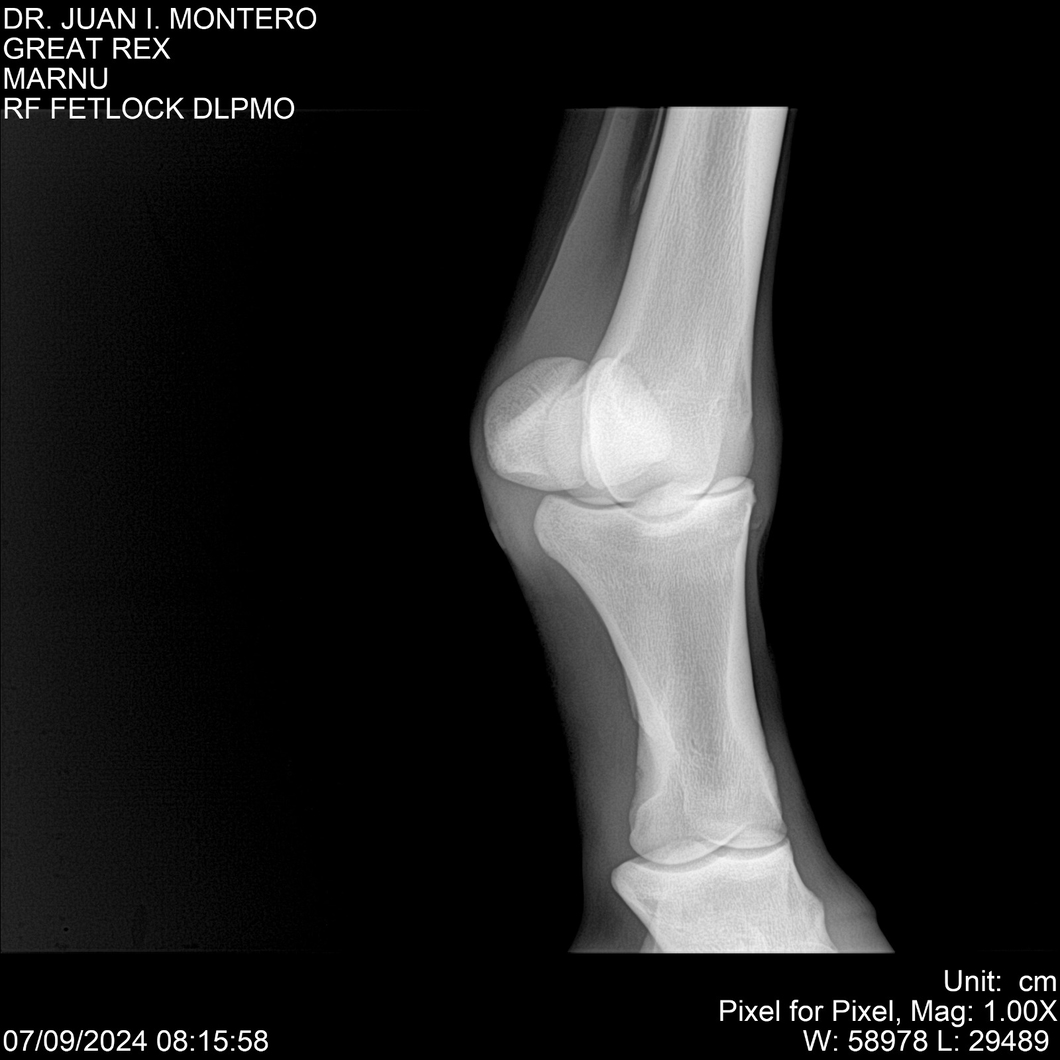

LOTE 4, GREAT REX Lote Anterior Volver al remate Lote Siguiente Ficha Contacto Montevideo - Ficha del Lote Identificador: #282518 Categoría: Yeguarizos Montevideo - 66 Visualizaciones ClicData Contacto Empresa: Abelenda N. R., Walter Hugo Nombre*: Teléfono* : E-mail* : Mensaje Enviar Registrese gratis Este contenido Exclusivo está disponible sólo para usuarios registrados Ingresar